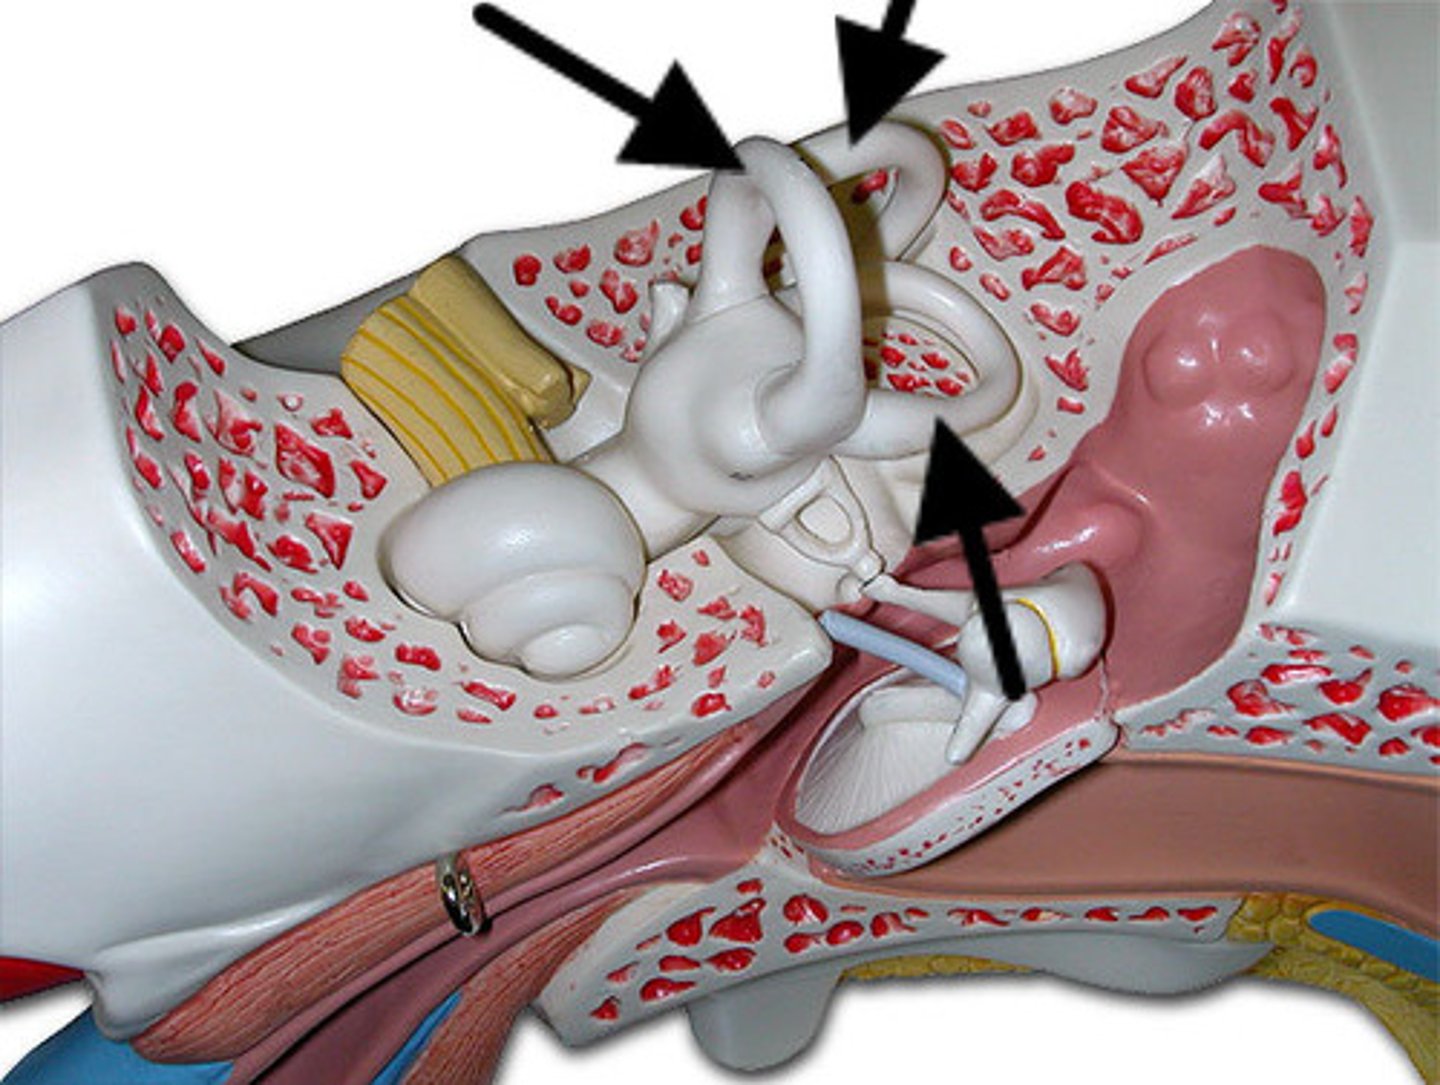

auditory ossicles

tympanic membrane

tympanic cavity

Eustachian tube

coclea

semicircular canals